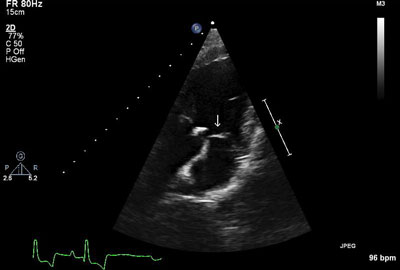

Imaging ResultsThoracic radiographs and abdominal ultrasound were unremarkable. Two-dimensional, M-mode, color flow, and spectral Doppler echocardiography demonstrated a vegetative lesion associated with the aortic valve, moderate aortic regurgitation, mild thickening of the mitral valve, and mild left atrial enlargement (Figures 1 and 2).

Figure 1 (above): Left parasternal long-axis view: A hyperechoic lesion associated with the aortic valve was noted (arrow), consistent with a vegetative endocarditis lesion.